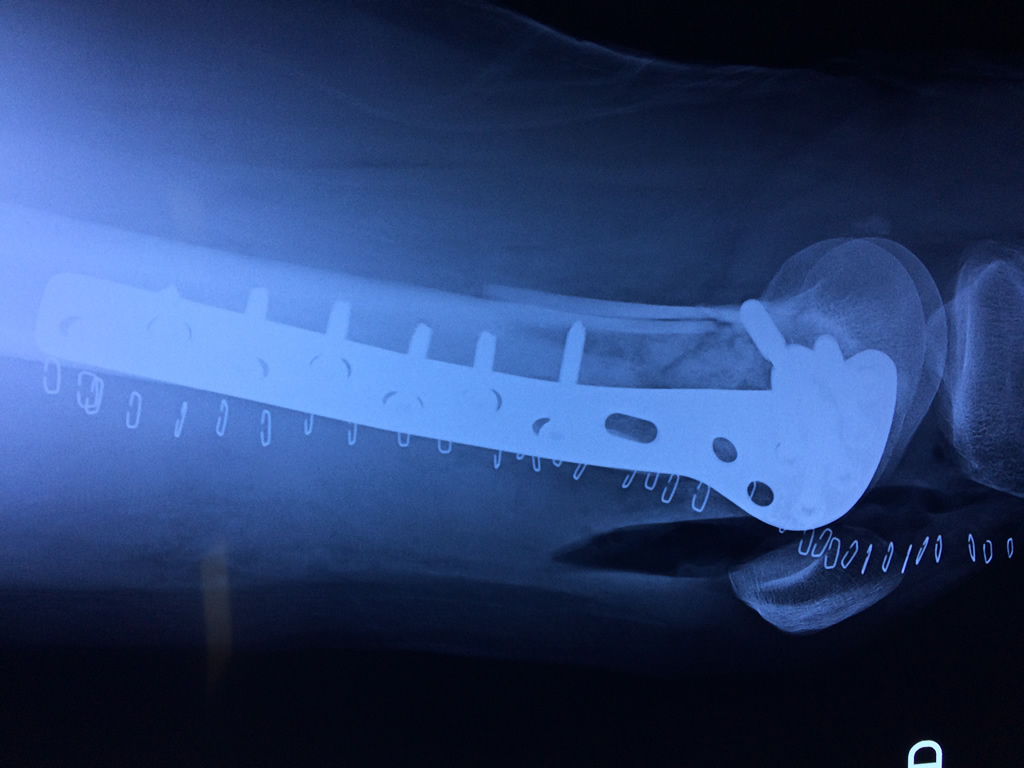

Cirugías de Quiste de Baker